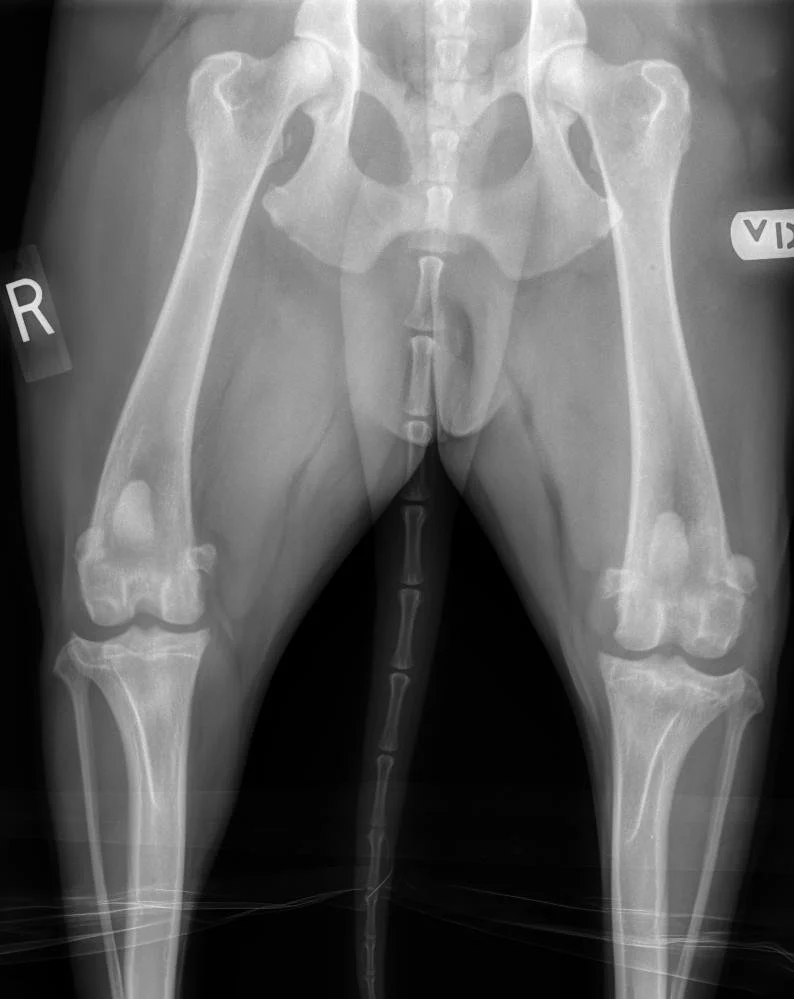

The plate and screws required to stabilize the bone after a tibial plateau leveling osteotomy (TPLO) are easily visible in a radiograph.

~$5000 per knee

TPLO Surgery: Mechanical Stabilization

The Tibial Plateau Leveling Osteotomy (TPLO) is widely considered the gold standard for large, active, or young dogs with complete CCL ruptures. The surgery involves a precise radial cut in the tibia to rotate the slope of the bone, effectively neutralizing the force that causes the femur to slide backward. Once the bone is stabilized with a specialized plate and screws, the ligament is no longer needed for the dog to walk normally.